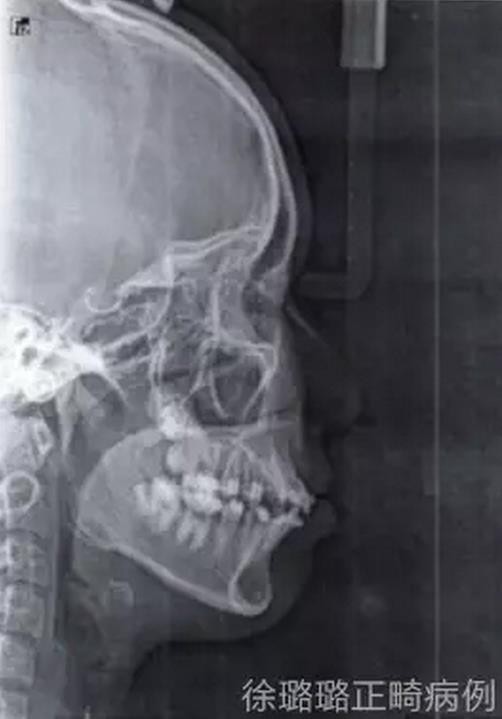

X 線檢查:替牙列,上頜雙側(cè)尖牙埋伏阻生(含牙囊腫),四顆第三恒磨牙牙胚存在。

前牙 CT 檢查:上頜雙側(cè)尖牙埋伏阻生——雙側(cè)尖牙的牙冠均在側(cè)切牙根方的唇向位。